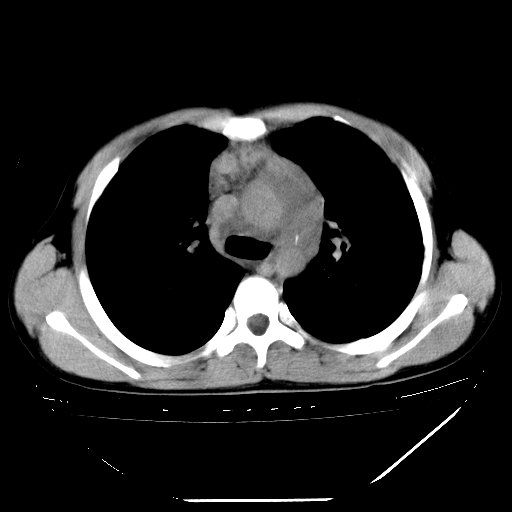

男,13岁,咳嗽、咳痰伴发热一周。

上纵隔课件多枚淋巴结,部分相互融合,左侧支气管壁增厚,肺纹理较右侧增粗,患者,男,13岁,

中上纵隔见多枚淋巴结肿大,部分相互融合成团片,左肺门增大,上叶支气管变窄,肺内多处斑片状 索条状及棉絮状致密影。临床“男,13岁,咳嗽、咳痰伴发热一周。”首先考虑:原发综合征!不除外淋巴瘤可能!

纵隔多发肿大淋巴结,部份有融合改变。双肺血管气管束增厚,以肺门为中心向外周散发,以左肺下叶为明显。考虑淋巴瘤可能性大。不除外原发综合征。

中上纵隔见多枚淋巴结肿大,部分相互融合成团片,左肺门增大,上叶支气管变窄,左肺支气管血管束增粗,可见磨玻璃样影。临床“男,13岁,咳嗽、咳痰伴发热一周。”首先考虑:淋巴瘤可能性大!

中上纵隔见多枚淋巴结肿大,部分相互融合成团片,纵隔内脂肪间隙模糊,左肺门增大,上叶支气管变窄,左肺支气管血管束增粗,可见磨玻璃样影。考虑纵隔淋巴管炎